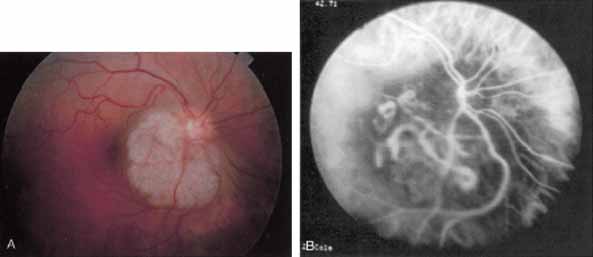

ICG angiography in amelanotic melanomas reveals variable blockage, depending on the amount of pigmentation present in the lesion. Corkscrew vessels have been identified with ICG angiography, but not with fluorescein angiography, in some patients with amelanotic melanoma80,81 (Fig. 24). The meaning of this vascular pattern currently is unclear, but it may eventually assist in the differentiation of these primary ocular tumors from metastatic lesions.

Fig. 24 A. Clinical photograph of a patient with an amelanotic melanoma adjacent to the optic nerve head. B. Mid-phase indocyanine green angiogram demonstrating corkscrew vessels within the melanoma.